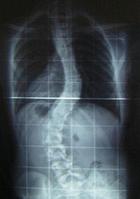

Також одним iз поширених захворювань опорно-рухового апарату у школярiв i сколiоз.

Хребет - це витончена структура, що збоку нагадуi витягнуту букву ВлSВ». Верхня частина спини нахилена назовнi, а нижня частина спини злегка вигнута всередину. Хоча якщо дивитися ззаду, хребет буде виглядати прямою лiнiiю вiд основи шиi до куприка. Сколiоз - це бiчне викривлення хребта. Вiн зтАЩявляiться й розвиваiться в перiод iнтенсивного зростання органiзму. Дитина росте не поступово, а толчкообразно, за порiвняно спокiйним перiодом може вiдзначатися перiод активного росту. Особливо це помiтно в перiод полового дозрiвання й у попереднiй йому. Саме в цей час може виявитися й бурхливо розвиватися деформацiя хребта. Наростання деформацii зауважують i батьки. РЖз закiнченням росту наступаi стабiлiзацiя процесу розвитку скривлення хребта. Перiод прогресування сколiозу збiгаiться з перебуванням дитини в школi. Тому найголовнiшi причину захворювання в неправильному навантаженнi на хребет при використаннi погано пiдiгнаноi парти, тривалому сидiннi за комптАЩютером. До зовнiшнiх ознак i симптомiв сколiозу вiдносяться:

Якщо кривизна сколiозу посилюiться, хребет теж починаi скручуватися або згинатися, на додаток до бiчного викривлення. Це призводить до того, що ребра на однiй сторонi тiла випирають назовнi, утворюючи реберний горб. На iншому боцi ж формуiться глибока западина, що разом деформуi тулуб. Важкий ступiнь сколiозу може викликати бiль у спинi i утруднене дихання.